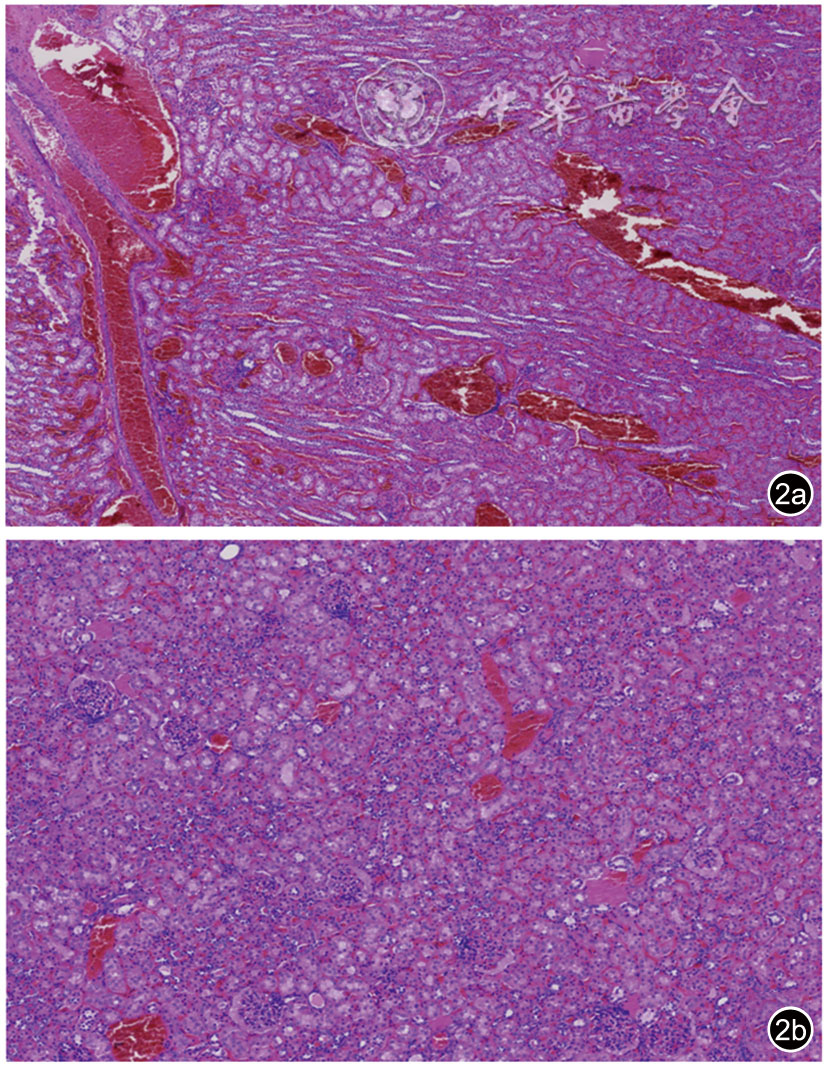

A total of 20 New Zealand White rabbits were used as the study subjects. At 2 hours after ligation of the left renal vein, Young's modulus was measured and compared across different sides (healthy side vs affected side), anatomical locations (upper pole vs mid portion vs lower pole), and organizational structures (cortex vs medulla vs renal sinus) of the kidney. The point-biserial correlation coefficient was employed to analyze the correlation between Young's modulus in various renal regions and the status of acute renal vein occlusion. The intraclass correlation coefficient (ICC) was used to assess the reproducibility of the Young's modulus measurements.

Regarding anatomical locations, in the healthy side group, the differences in Young's modulus were statistically significant between the upper pole and mid portion, and between the mid portion and lower pole (P<0.05). In the affected side group, no statistically significant differences in Young's modulus were observed among the upper pole, mid portion, and lower pole (P>0.05). Regarding organizational structures, in the healthy side group, the differences in Young's modulus were statistically significant between the cortex and renal sinus, and between the medulla and renal sinus (P<0.05). In the affected side group, the differences in Young's modulus among the cortex, medulla, and renal sinus were all statistically significant (P<0.05). Three-way ANOVA revealed that the three-way interaction effect (acute renal vein occlusion status × anatomical location × organizational structure) was not statistically significant (F=1.575, P=0.190). The Young's modulus values in the affected side group were consistently higher than those in the healthy side group for identical anatomical locations and organizational structures, and all these differences were statistically significant (P<0.05). Among these comparisons, the mid-portion cortex demonstrated the most prominent effect size (Cohen's d=2.770), eexhibited the strongest correlation with acute renal vein occlusion (r=0.867), and showed the optimal measurement reproducibility (ICC=0.987).